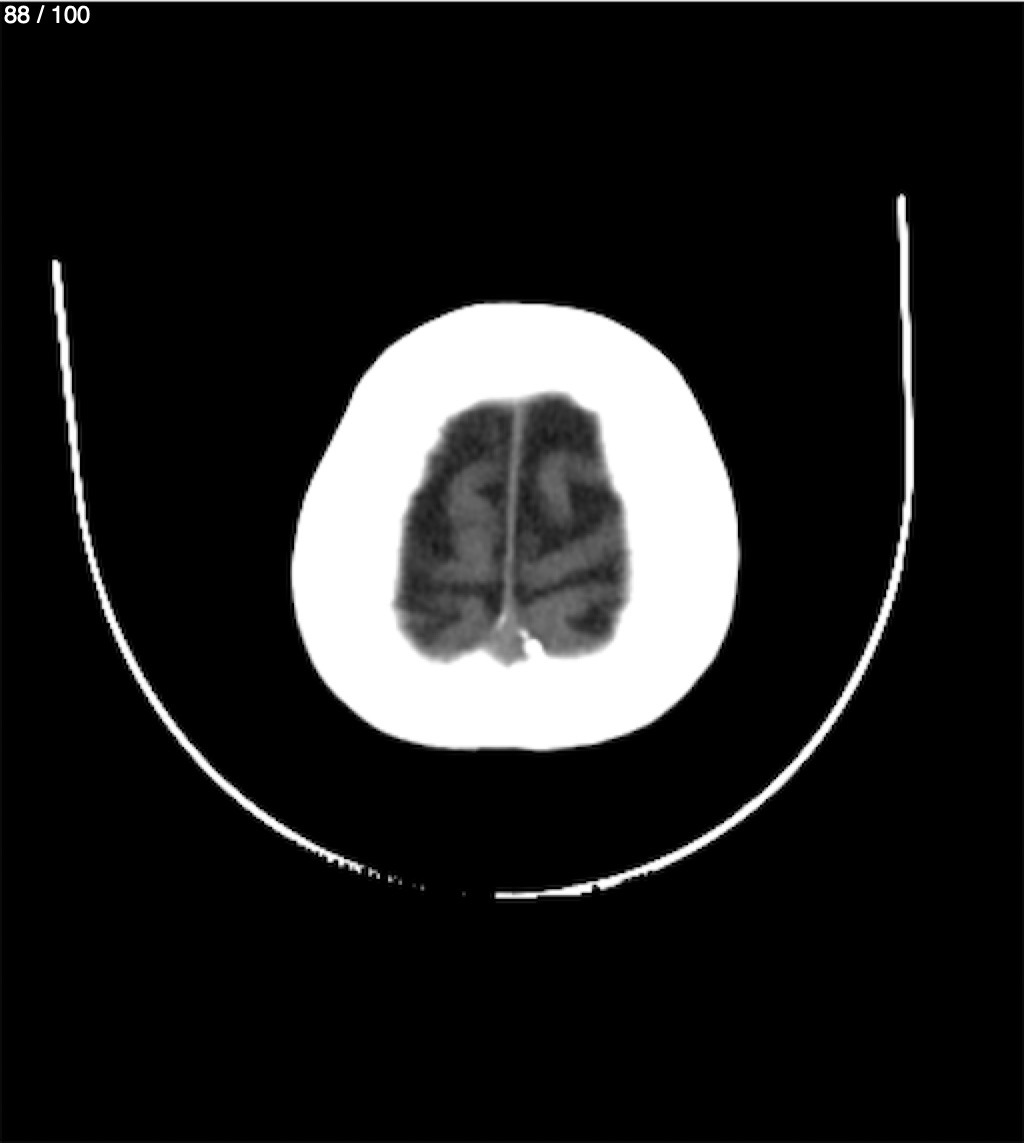

Catarino Perez Escobar 85A - T.C Craneo